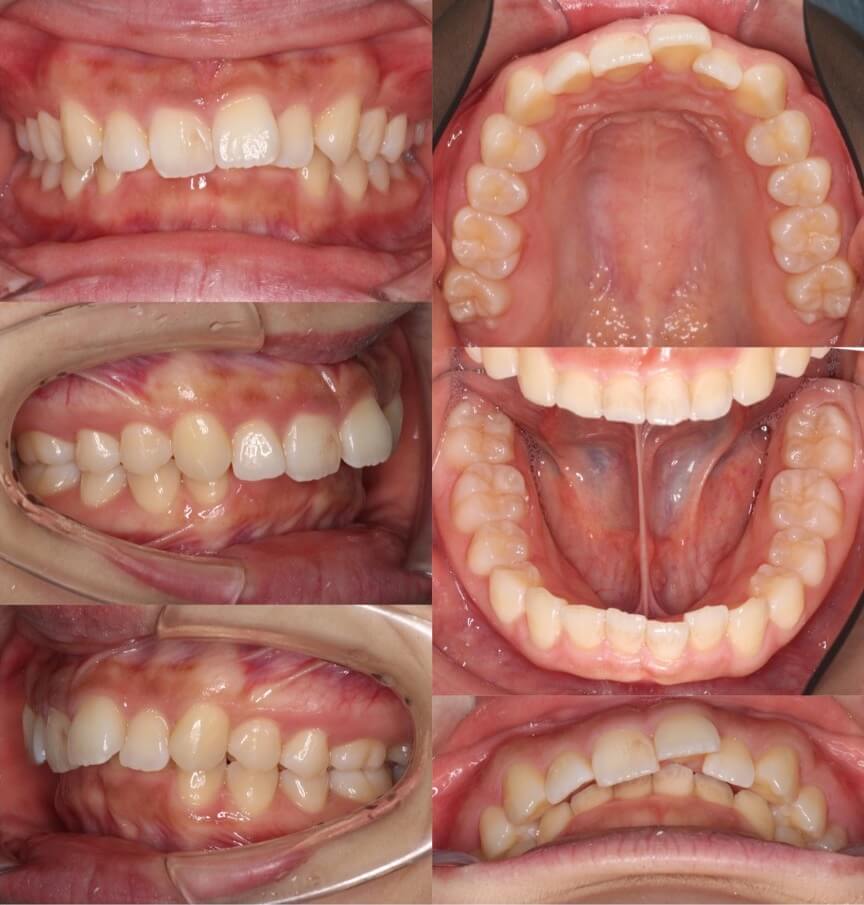

20代女性・マウスピース型装置

過蓋咬合の改善は見た目の変化は少ないのですが、口の中の歯並びの変化は大きいです。下の歯並びが見えるようになり正しいかみ合わせになりました。

<症例概要>

主訴:前歯のかみ合わせが悪い

年齢・性別:大学生女性

住まい:千葉県佐倉市

症状:過蓋咬合・右5番シザーズバイト・下顎叢生

治療方針:下顎前歯唇側傾斜による圧下

治療装置:マウスピース型矯正装置(アライナー装置)

アライナー枚数:43+27

治療期間:1年4か月

リテーナー:上下クリアタイプ

治療費用:990,000(税込)

代表的副作用:痛み・治療後の後戻り・歯根吸収・歯髄壊死・歯肉退縮

▶︎その他の副作用

【治療シミュレーション】

主に下の歯並びを前方に倒しながら歯茎方向に沈め(圧下)させ、過蓋咬合を改善していきます。

大学生男性・唇側矯正装置・4本抜歯